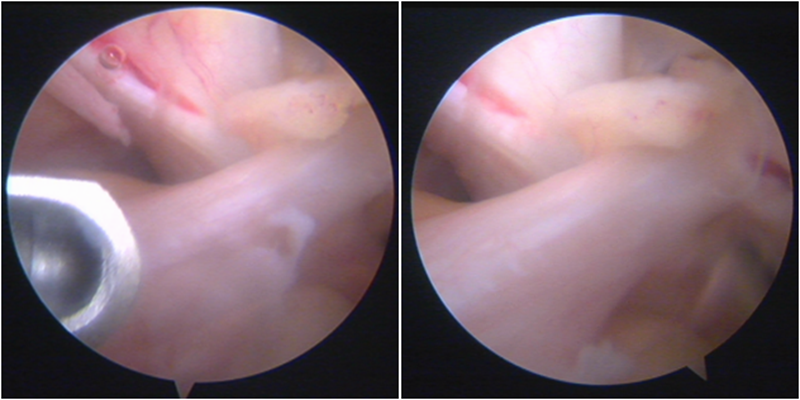

镜下显示ACL残束

内侧半月板

外侧半月板